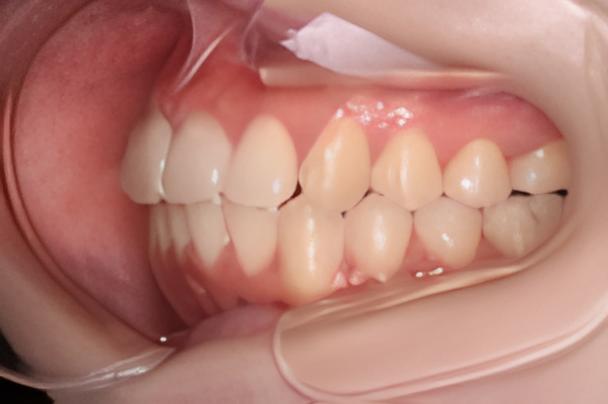

術前と術後の変化

お口全体の変化